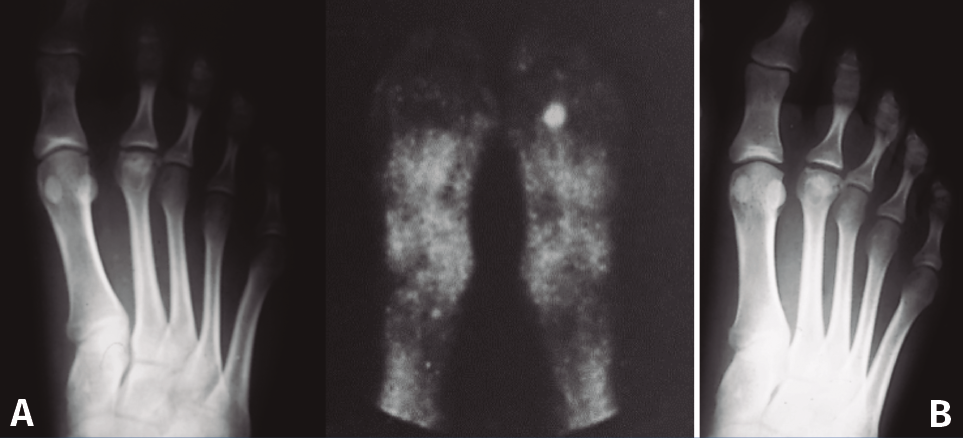

Figura 5. Tratamiento conservador. Paciente tratada con plantilla de descarga. A: imágenes al inicio del tratamiento; B: 2 años más tarde, mínima afectación articular.

En las fases iniciales (estadios 1 y 2 de Smillie) en las que, tal como se ha comentado, las molestias del paciente son inexistentes o leves, están indicadas las plantillas ortopédicas de descarga de la cabeza metatarsal afecta, los antiinflamatorios no esteroideos (AINE) y la electroterapia antiinflamatoria durante la crisis de dolor. Se recomienda al paciente disminuir la práctica deportiva de impacto(11,17). Con ello se consigue que, cuando se finaliza la fase de reparación, la deformidad sea la menor posible (Figura 5).